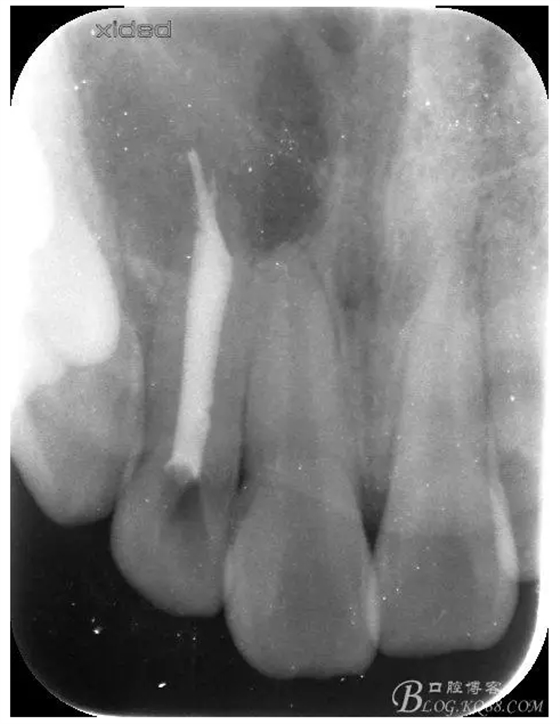

1.術前的根尖片檢查及根管治療影像: